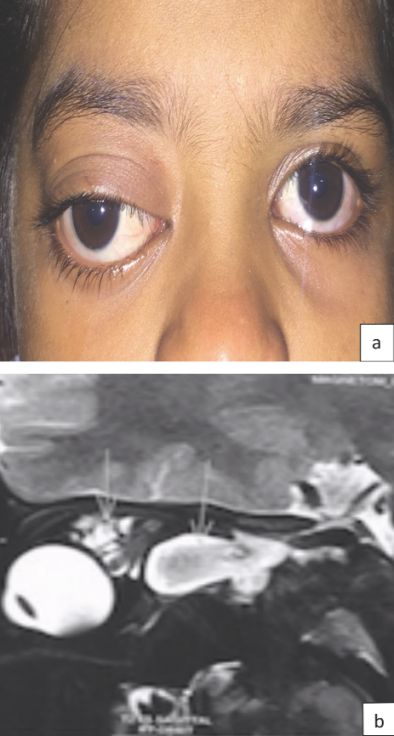

A 6-year-old girl came to us with complaints of acute prominence of her right eye since 10 days. The child has had blurred vision in the right eye since then. The parents gave history of previous prominence of the right eye which aggravated with respiratory tract infection (Figure 1 [Fig. 1]). On examination, the child had a downward and outward proptosis in her right eye. Her vision in the left eye was normal (6/6: n6), and the right eye had hand movement vision. Pupillary examination in the right eye showed relative afferent pupillary defect. The patient’s anterior segment examination was otherwise normal in both eyes. Fundus examination in the left eye was normal, and the right eye retina showed choroidal folds. MRI orbit showed multiple cystic lesions occupying the entire right orbit. Based on the history and MRI findings, we diagnosed the case as lymphangioma with bleeding and optic nerve compromise. Intravenous methylprednisolone 1 g was started immediately and was continued for three days. Meanwhile, cyst aspiration and bleomycin injection was planned in order to reduce the compressive effect on the optic nerve by the cyst.

Figure 1: a) Clinical picture of the patient with down and out proptosis; b) MRI orbit sagittal view showing cystic component of lymphangioma above and below the optic nerve